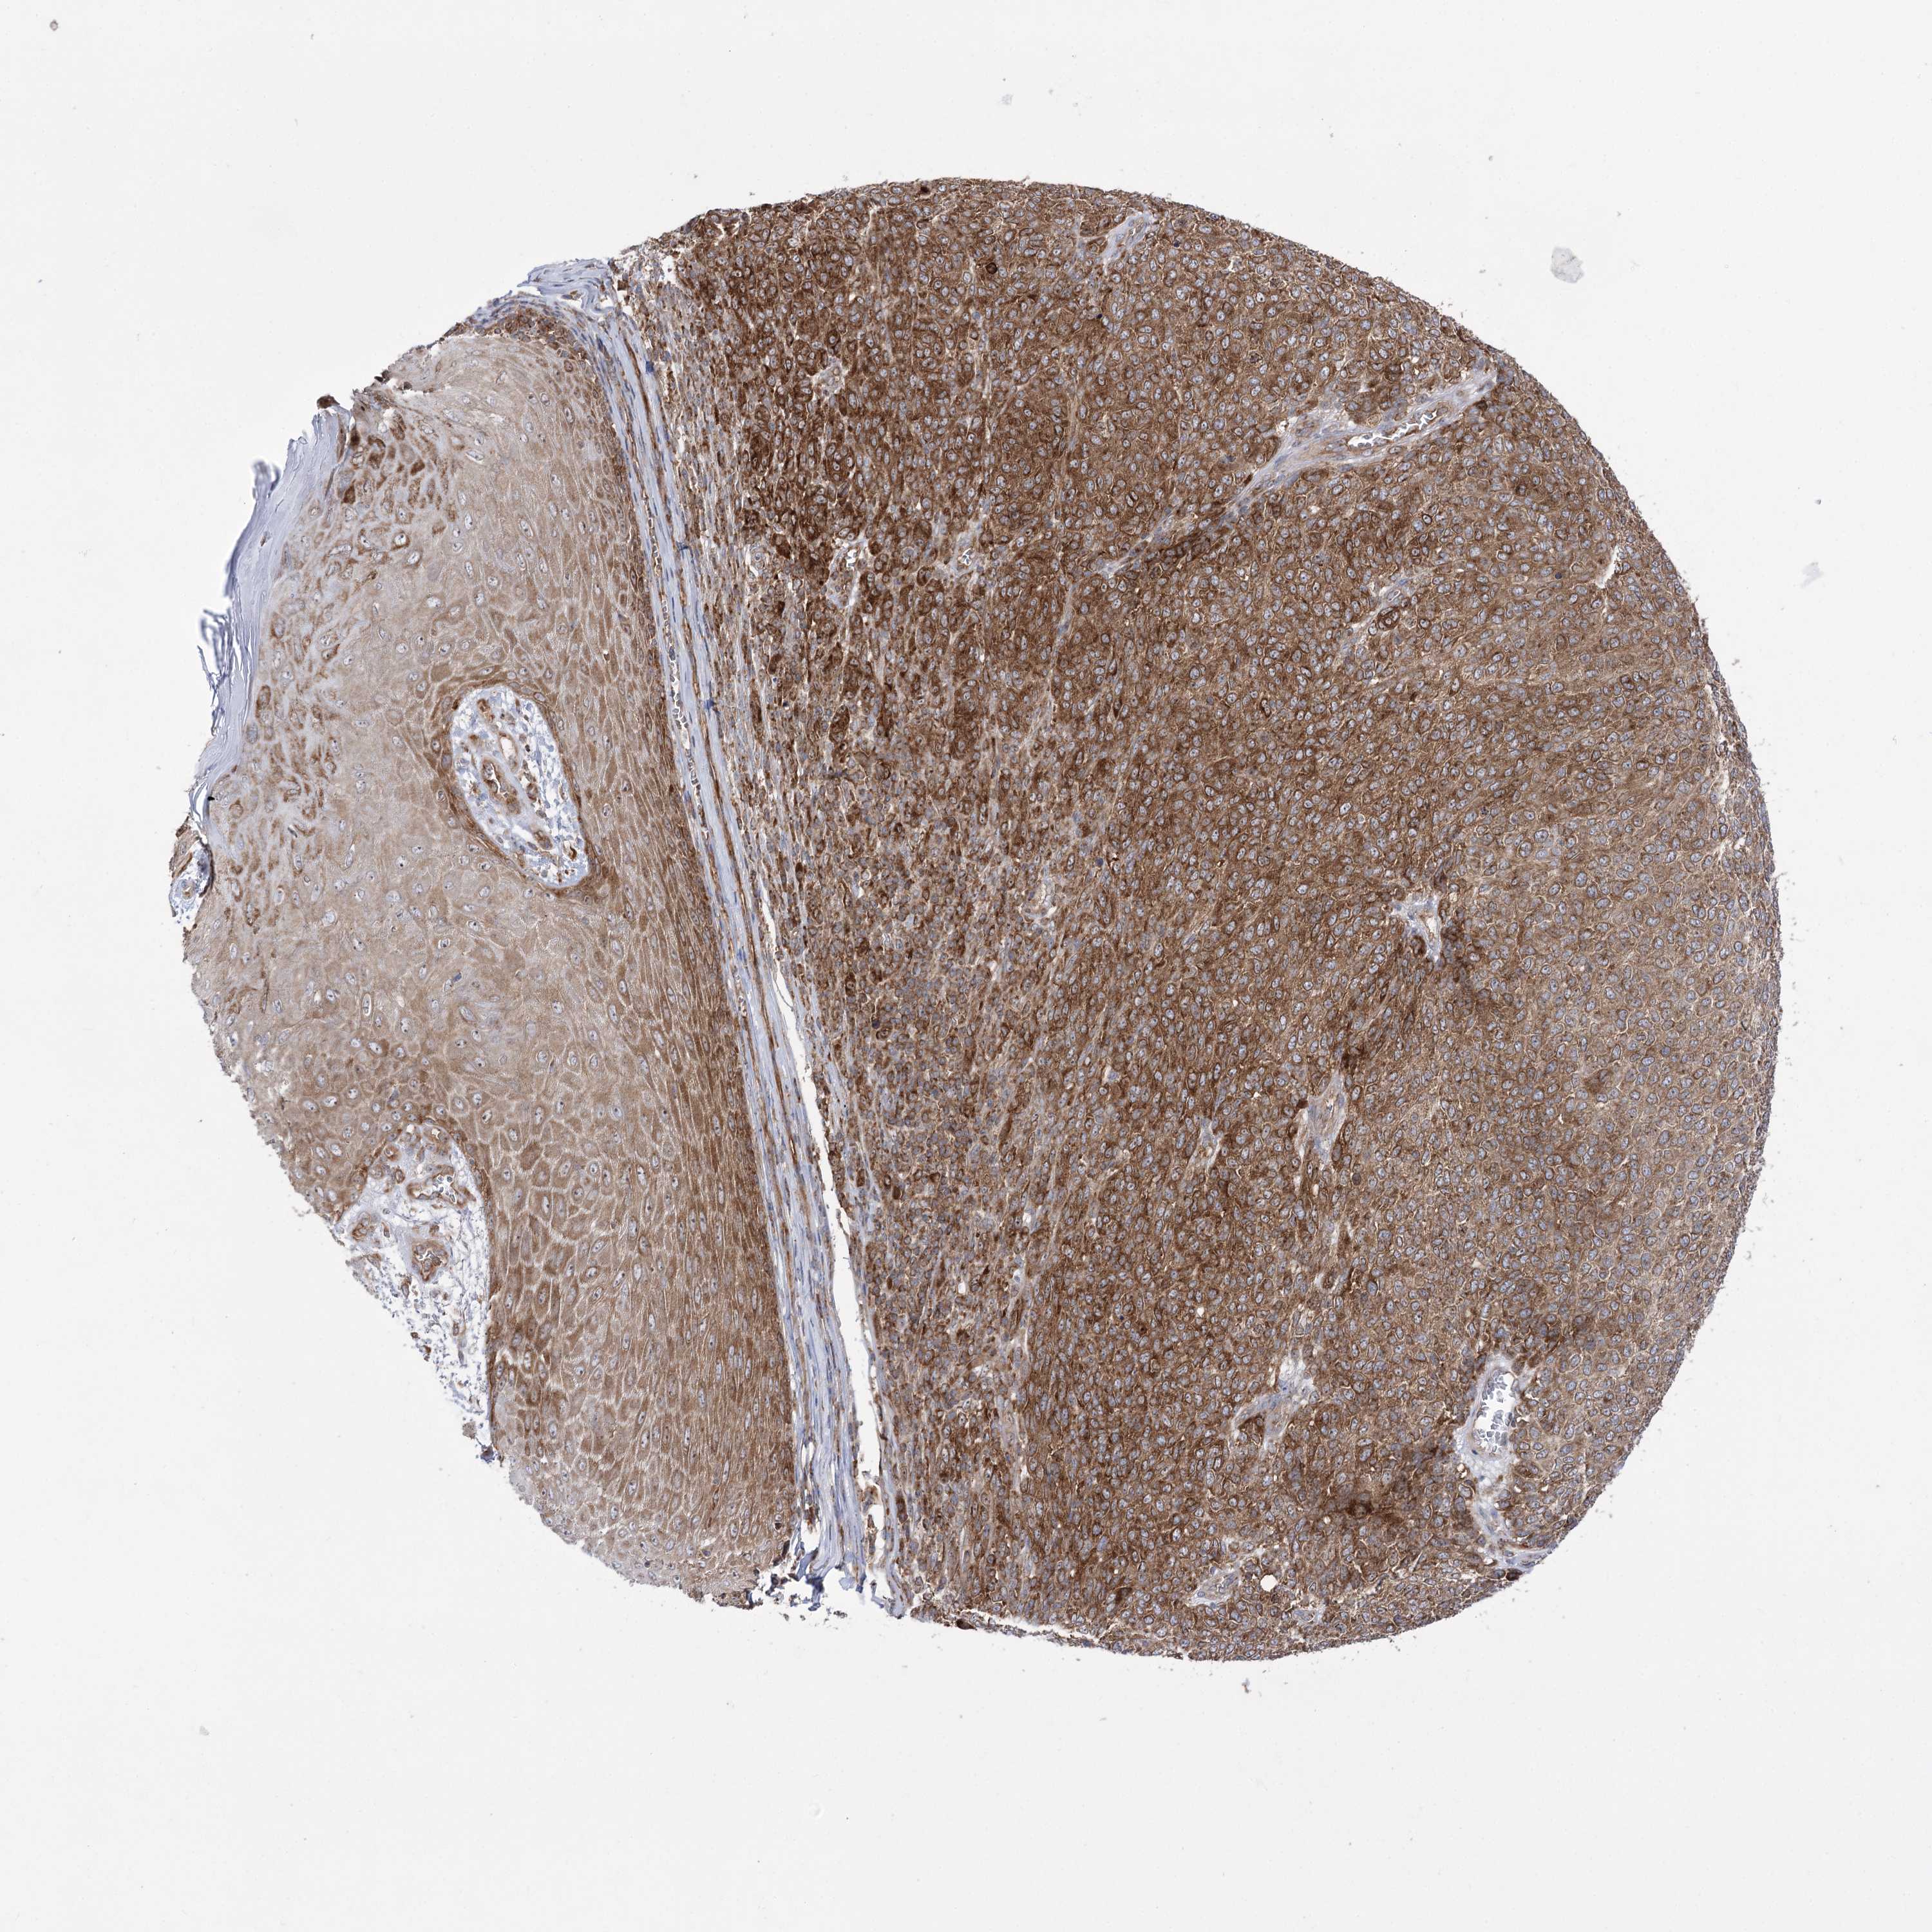

MELANOMA - Protein expressioni

A mouse-over function shows sample information and annotation data. Click on an image to view it in a full screen mode. Samples can be filtered based on level of antibody staining by selecting one or several of the following categories: high, medium, low and not detected. The assay and annotation is described here.

Note that samples used for immunohistochemistry by the Human Protein Atlas do not correspond to samples in the TCGA dataset.

Antibody stainingi

Antibody staining in the annotated cell types in the current human tissue is reported as not detected, low, medium, or high, based on conventional immunohistochemistry profiling in selected tissues. This score is based on the combination of the staining intensity and fraction of stained cells.

Each image is clickable and will lead to virtual microscopy that enables deeper exploration of all samples and also displays staining intensity scores, fraction scores and subcellular localization as well as patient and tissue information for each sample.

Antibody HPA036514

Antibody HPA036515

Staining

High

Medium

Low

Not detected

Intensity

Strong

Moderate

Weak

Negative

Quantity

>75%

75%-25%

<25%

None

Location

Nuclear

Cytoplasmic/membranous

Cytoplasmic/membranous,nuclear

Malignant melanoma, NOS

Malignant melanoma, Metastatic site